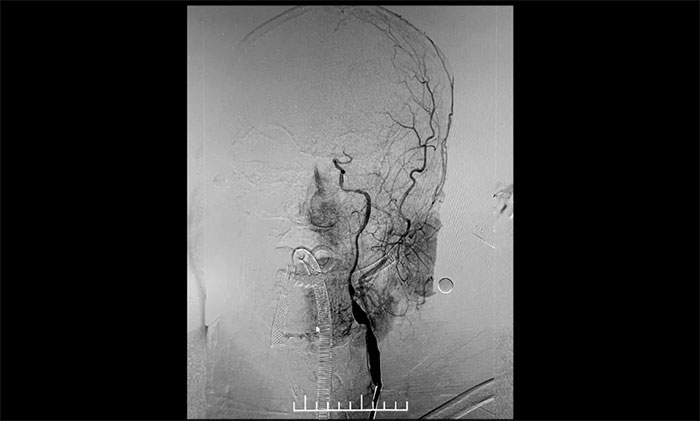

患者為老年男性,因言語不利,伴右側肢體活動不利入院。外院行頭顱CT檢查:雙側腦室旁及基底節(jié)區(qū)腔隙灶。入院后,頭顱MRI平掃+DWI+MRA提示,腦干、雙側小腦及雙側大腦半球多發(fā)腔梗、缺血灶;MRA:腦動脈硬化,左側頸內(nèi)動脈不完全閉塞,右側頸內(nèi)動脈C3-C6段、右側大腦中動脈M2段多發(fā)狹窄。“主動脈弓+全腦動脈造影”提示:右頸內(nèi)動脈起始段重度狹窄,左頸內(nèi)動脈起始段重度狹窄,串聯(lián)左頸內(nèi)動脈巖骨段中度狹窄,左頸內(nèi)動脈眼動脈段閉塞。

▲ 左頸內(nèi)動脈起始段重度狹窄,并串聯(lián)多處狹窄、閉塞